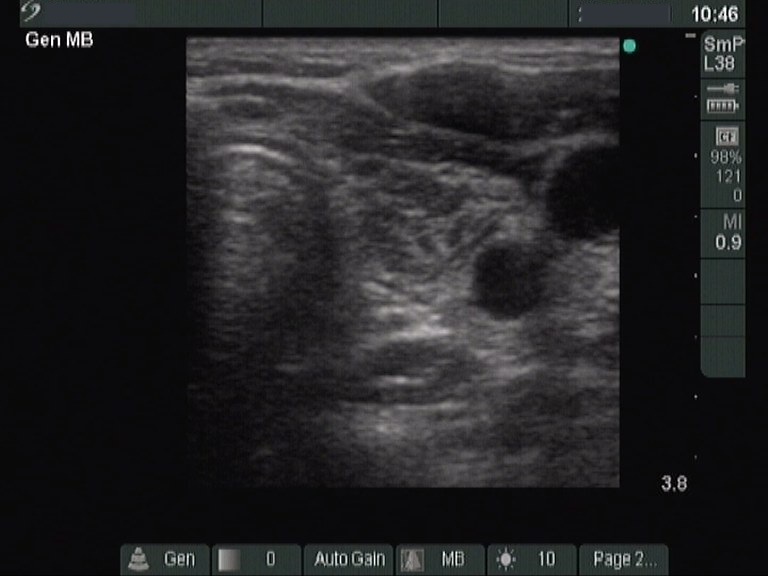

Ultrasonography: revealed hypoechogenic inhomogeneous thyroids. There was a moderately hyperechogenic nodule in the left lobe. The nodule presented a halo sign and perinodular blood flow.